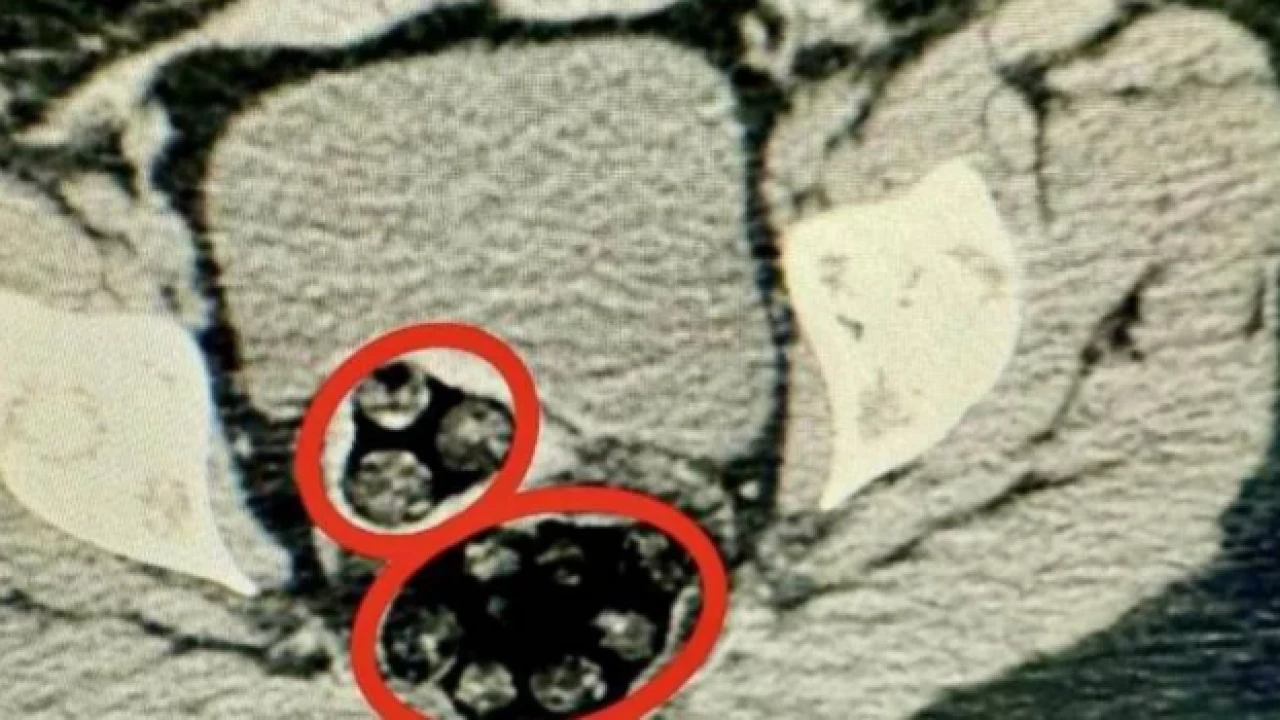

Kars'ta, polisin durdurduğu yolcu otobüsünde hareketinden şüphelenilen İran uyruklu yolcunun hastanede çekilen röntgeninde, makatında uyuşturucu tespit edildi. Uyuşturucu doğal yolla çıkarılırken, şüpheli tutuklandı.

Kars Harakani Devlet Hastanesi'ne götürülen Yenkejeh'in çekilen röntgeninde, makatında uyuşturucu tespit edildi. Doğal yolla kadının makatından 94 parça halinde toplam 550,93 gram metamfetamin çıkarıldı.